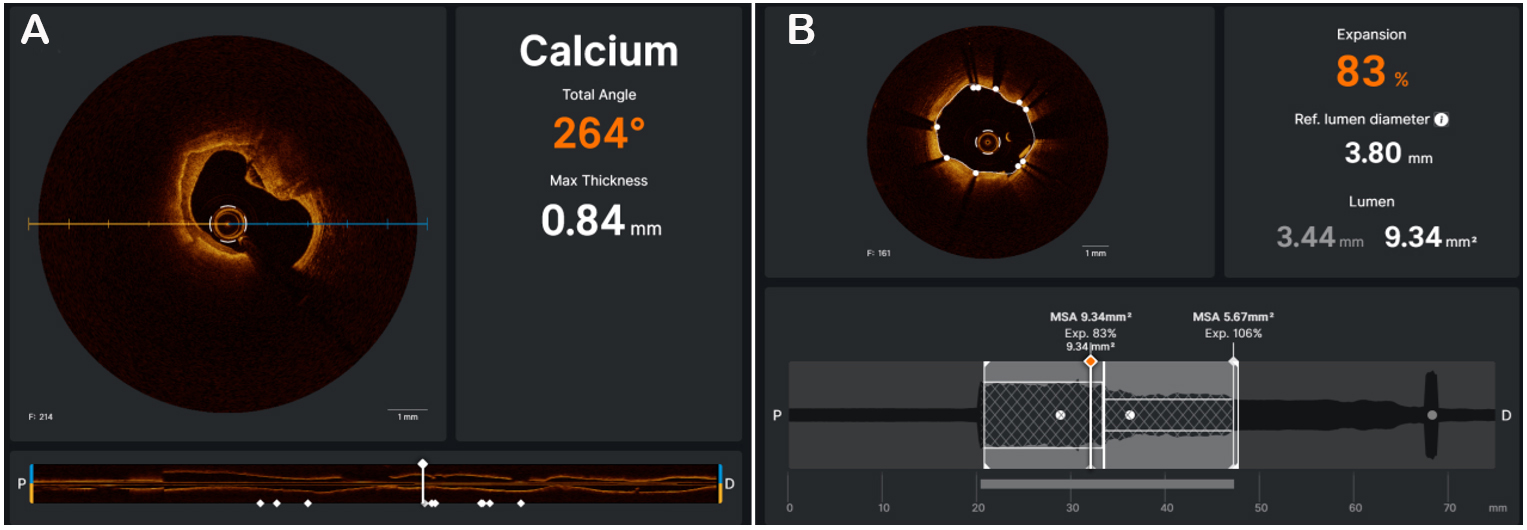

On optical coherence tomography (OCT) imaging, calcium appears thin, with a low-intensity signal area and well-delineated sharp borders[21] [Figure 4]. Thanks to its higher resolution (10 to 20 µm), OCT is able to quantify calcium thickness and show calcium disruption; its sensitivity and specificity for CAC are

Figure 5. The OCT software (UltreonTM, Abbott, Illinois, US) is able to automatically measure the maximum calcium thickness and total angle of calcium (A). OCT can check the result, automatically calculating stent expansion and minimal stent area (B).

A recent study conducted by Fujino et al. presented an OCT score to classify calcium plaques with a numerical cut-off; calcium arc > 180° (2 points), calcium length

Like IVUS, OCT is helpful in the planning of PCI, to choose a possible adjunctive intracoronary device dedicated to modify CAC by ablating its surface and breaking its integrity (fractures and discontinuities)[22]. OCT can check the effects of calcium debulking, identifying the presence of calcium fractures, which seem to be related to larger stent expansion and better procedural outcomes. The results of two recent studies suggested that CAC with extensive circumferential length and minor minimum axial thickness tended more to crack after conventional PCI[35,36]; these findings supported a dominant role of OCT in determining which calcium plaques need additional lesion preparation.

Finally, OCT can assess post-stent implantation by checking the presence of stent malapposition, measuring the distance between the abluminal surface of the strut and the luminal surface of the artery wall[37], edge dissections, and stent expansion [Figure 5B].